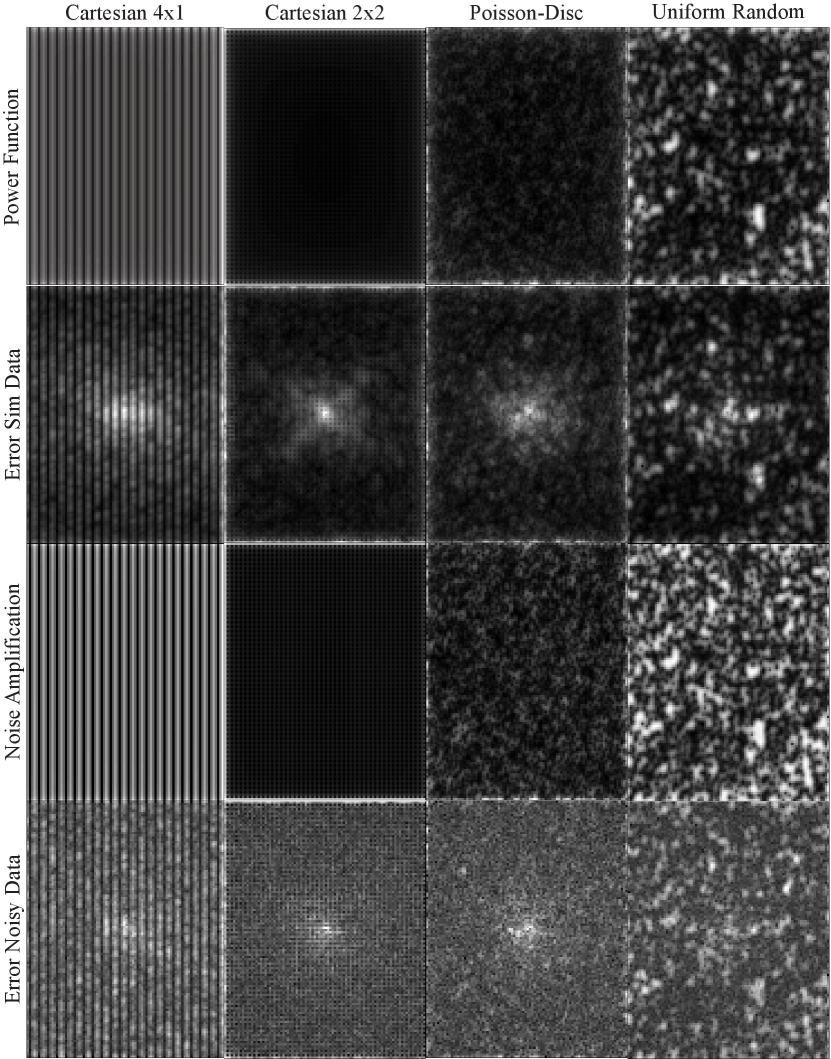

Refer to caption

Figure 4: Reconstructed images and corresponding error maps for Cartesian, Poisson-disc, and uniform random sampling for simulated (top) and noisy data (bottom). All sampling schemes used an undersampling factor of 4. Error maps have been scaled by a factor of 40 (simulated) and 4 (noisy) to aid visibility.

Figure 2 shows the coil image and the corresponding sensitivity map for all receive channels as well as the combined image. Figure 3 shows the combined power function and the Frobenius norm of the cardinal functions for different sampling patterns. While for Cartesian 2×2222\times 2 and Poisson-disc sampling the power function is small everywhere inside the sampled region indicating that interpolation error is small, the situation is different for Cartesian 4×1414\times 1 and uniform random sampling: Where larger gaps appear in the sampling pattern, the power function has high values. The power functions themselves are bounded by the diagonal elements of the kernel. This bound is approached in regions where the cardinal functions go to zero, i.e. far from acquired samples, and corresponds to a situation where nothing is known about the k-space value. The bound for the combined power functions is 6.55306.55306.5530 for the kernel used here. Consistent with this upper bound, the maximum values observed near the boundary in the computed maps are 6.48026.48026.4802 for Cartesian 4×1414\times 1, 6.39216.39216.3921 for Cartesian 2×2222\times 2, 6.37976.37976.3797 for Poisson-disc, and 6.42776.42776.4277 for uniform random sampling. Computing the maximum in a smaller inner region of size 305×230305230305\times 230 far from the boundary, the maximum values are 0.61540.61540.6154, 0.052520.052520.05252, 0.10870.10870.1087, and 4.33034.33034.3303, respectively. The last number highlights the fact that high values are attained even inside the sampled area for uniform random sampling. While the error bound for Poisson-disc sampling is twice as large as for the Cartesian 2×2222\times 2 pattern, it is still very small, i.e. 60×60\times smaller than the maximum which is obtained in unsampled regions. The reconstruction results (Fig. 4) for noise-less data confirm that the interpolation error is lower for Cartesian and Poisson-disc than for uniform random sampling. Cartesian 4×1414\times 1 performs worse than Cartesian 2×2222\times 2, confirming the notion that it is usually better to distribute the acceleration along different phase-encoding directions. The structure of the error maps in k-space is predicted well by the power function for all sampling patterns (Fig. 5). It has to be noted that the power function yields only a worst-case bound (scaled by the norm of the data) which depends on the sampling pattern, but not on the actual signal. In contrast, the actual error values in k-space depend on the energy distribution of the signal and are much higher in the k-space center than in the periphery.

In addition to the interpolation error, noise is amplified during the reconstruction. Assuming Gaussian white noise, this effect is described by the Frobenius norm of the cardinal functions. In Nyquist-sampled regions, if all channels contribute equally one would expect a value of 1/N1𝑁\sqrt{1/N} because the data from all channels is averaged. Values can be much higher in case of undersampling, but can also be lower for regions very far from acquired samples. This can be seen in at the boundary of the computed maps shown in Figure 3. In agreement with the higher values of the Frobenius norm for Cartesian 4×1414\times 1 and uniform random sampling, the respective reconstruction results for the noisy data show much more noise in the reconstructed image. Again, the distribution of noise and errors in k-space has the same structure as the Frobenius norm of the local reconstruction operators and the power function predict (Fig. 5).